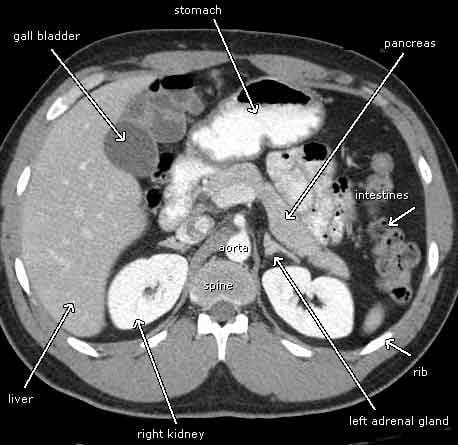

La vesícula biliar constituye un saco en forma de pera, conectada al sistema biliar extrahepático mediante el conducto cístico. Tiene como función almacenar la bilis producida por el hígado.

Los conductos biliares derecho e izquierdo abandonan el hígado por el hilio hepático para formar el conducto hepático. Éste se une al cístico y forman el colédoco que desemboca en la ampolla de Vater.

– Topograma: En AP. Se programan cortes axiales desde la cúpula hepática hasta el polo inferior de la vesícula o la terminación del colédoco (incluyendo la cabeza del páncreas).